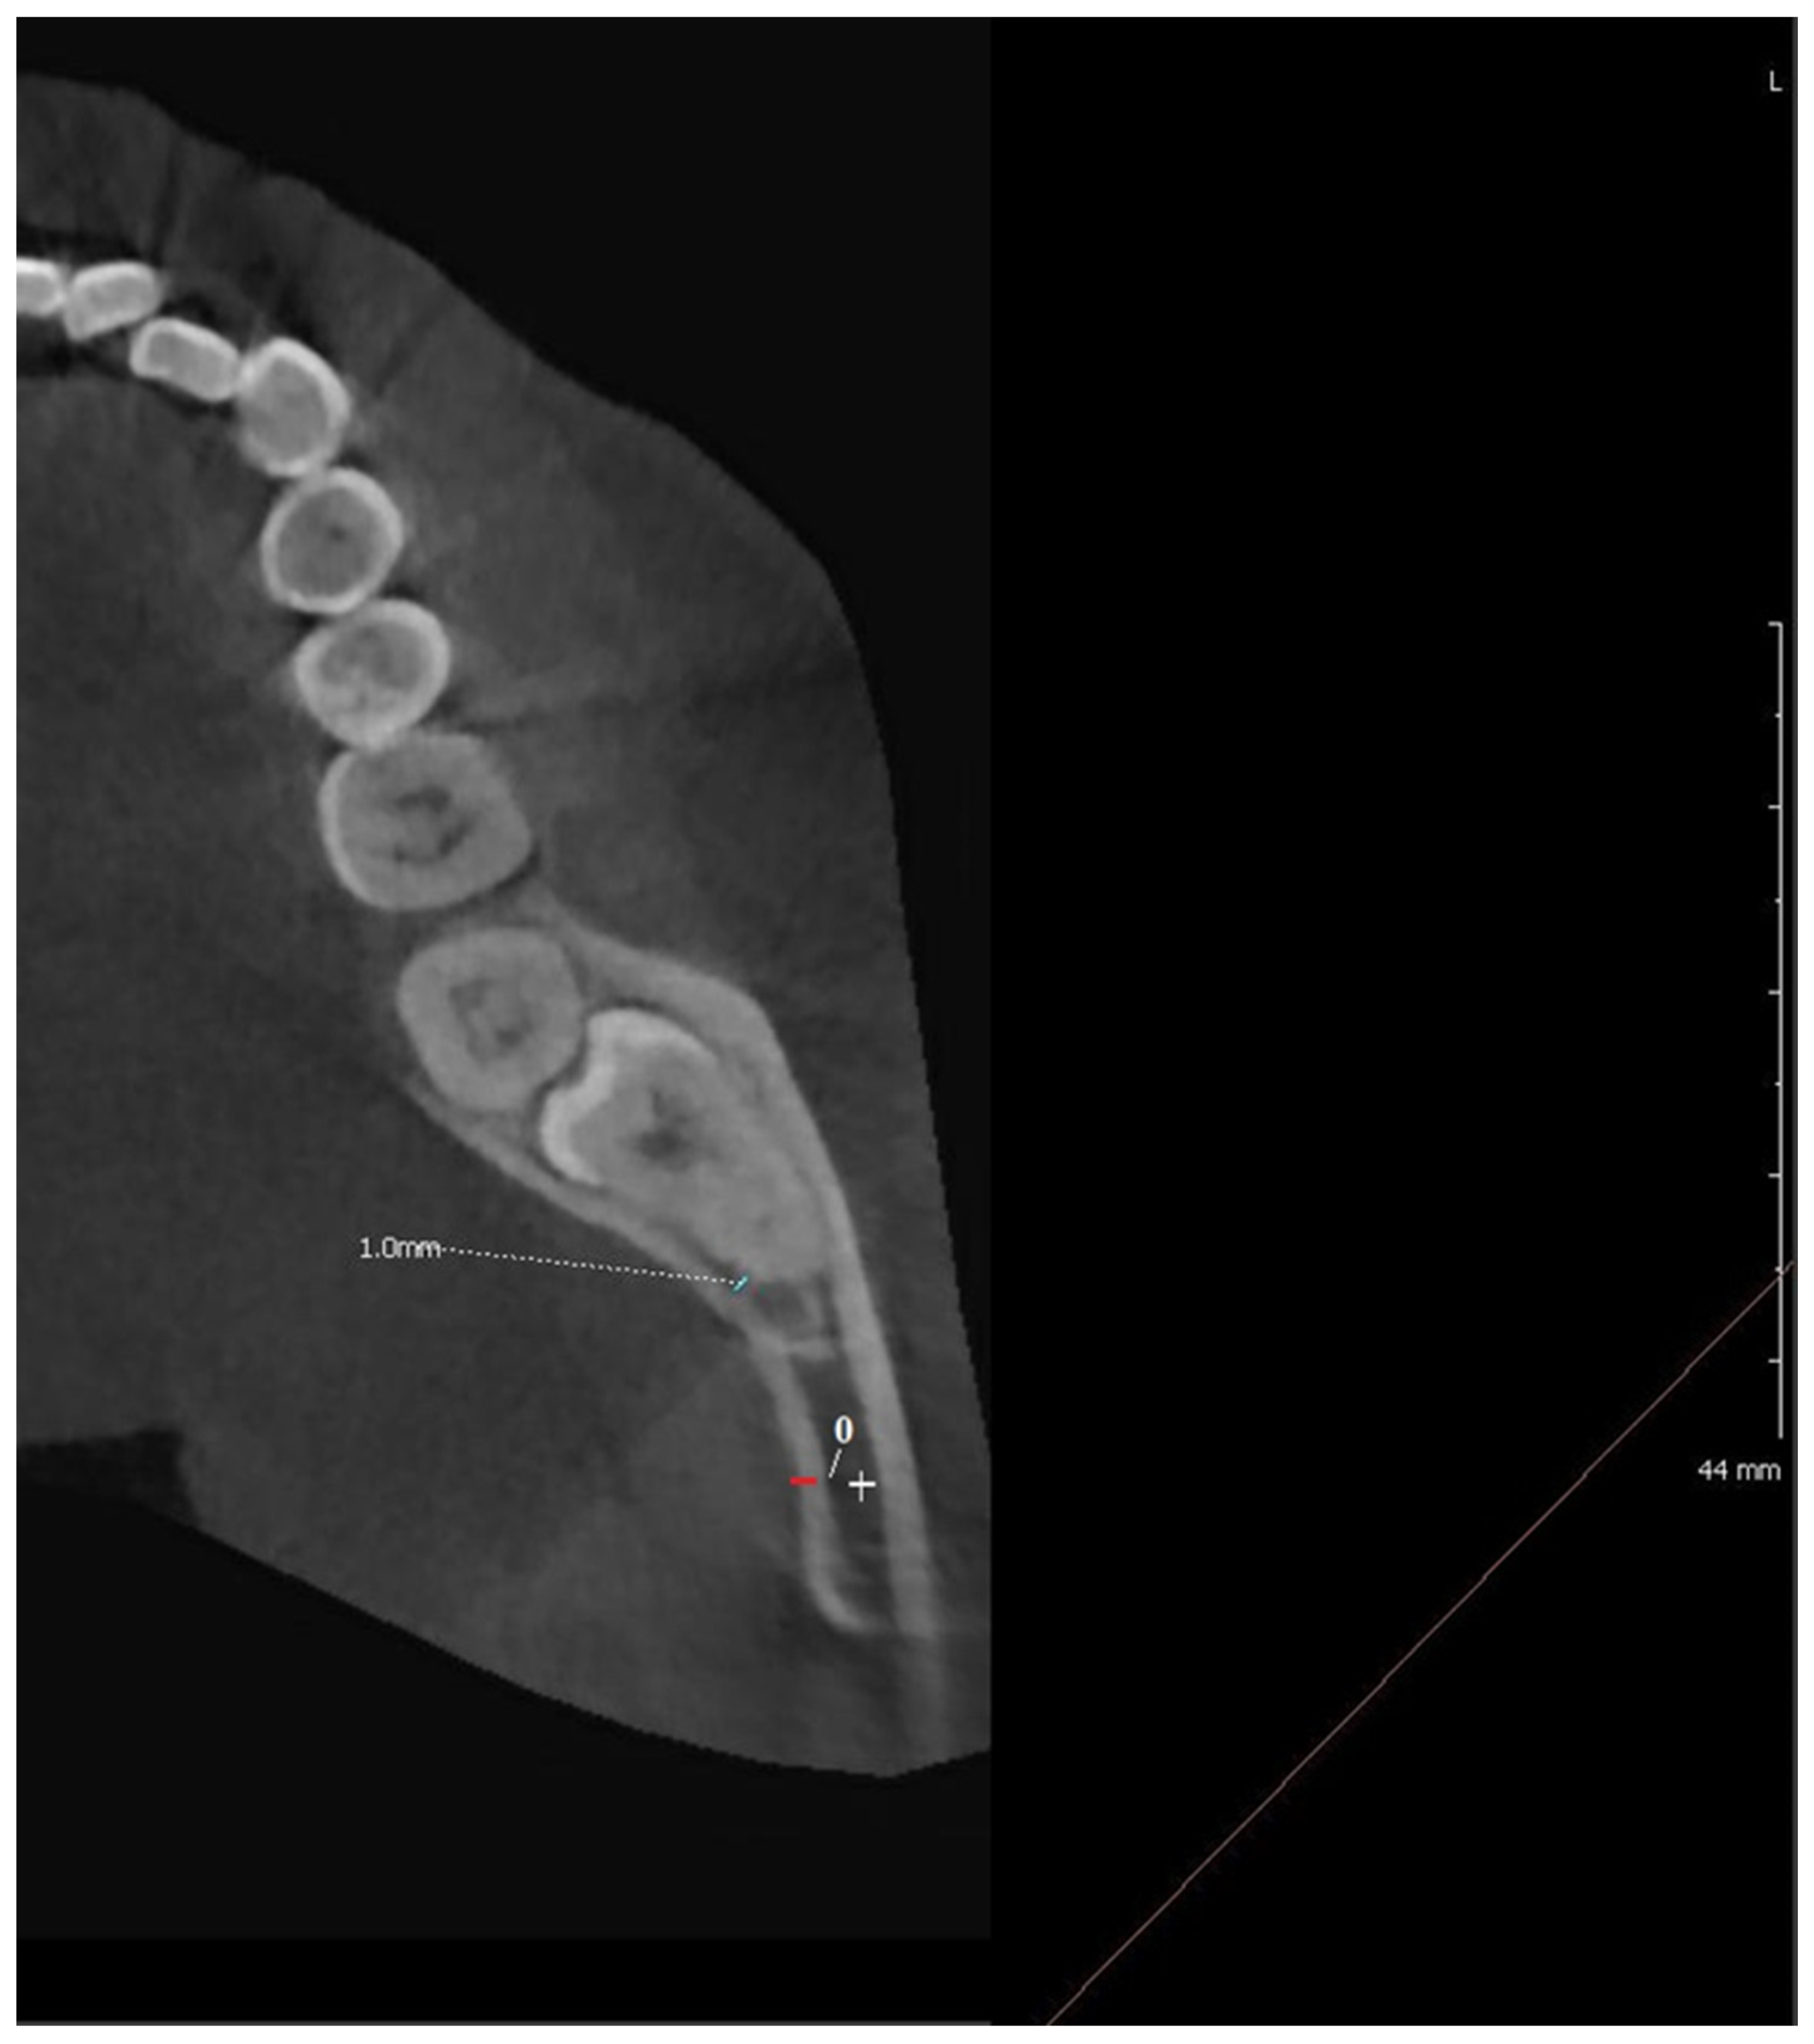

- True sign (Y-sign): the pre-operative OPG shows a band-like radiolucent sign corresponding to the apical portion of the root of the inferior third molar with no sign of other reason that could explain this. On CBCT image lingual impaction of the root is observed.

- False sign (F-sign): OPG image shows a band-like radiolucent area corresponding to the apical portion of the root of the inferior third molar and determining causes of the radiolucent area visible on OPG and CBCT such as Juxta-Apical Radio-Translucency, peri-apical lesion, immature apex, impaction of the inferior alveolar nerve into the lingual plate, apex impaction into the buccal plate.